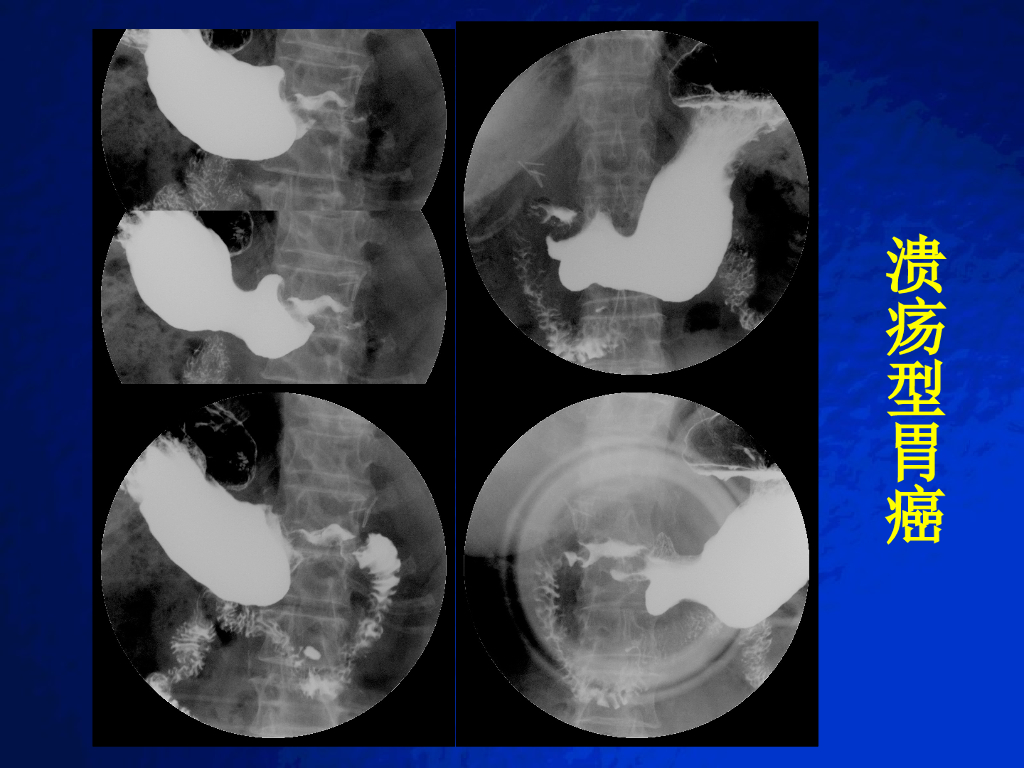

《放射诊断学》胃肿瘤实习.pdf